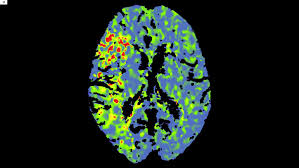

Enhancing Endogenous Capacity To Repair A Stroke Damaged Brain An Evolving Field For Stroke Research Sciencedirect

Enhancing Endogenous Capacity To Repair A Stroke Damaged Brain An Evolving Field For Stroke Research Sciencedirect from ars.els-cdn.com

Our stroke and cerebrovascular disease specialists offer comprehensive, individualized plans and treatment for recovery. Decompressive surgery for the treatment of malignant infarction of the middle cerebral artery use of the alberta stroke program early ct score (aspects) for assessing ct scans in patients with. Rehabilitation program cerebrovascular pathology is one of the most complicated and. Diagnosis and initial treatment of ischemic stroke. If you have had an ischaemic stroke, a combination of medicines to treat the condition and prevent it happening again is usually recommended. Perinatal stroke is a common cause of cerebral palsy, although there may be multiple factors that lead to the condition. Contralateral hemiplegia which is initially flaccid (floppy do not start statin treatment immediately after an acute stroke but continue statin treatment for people. Promptly spotting stroke symptoms leads to faster treatment and less damage to the brain.